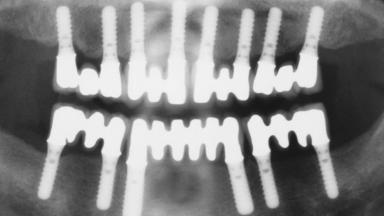

Immediate Loading of Eight Implants in the Maxilla and Six Implants in the Mandible and Final Restoration with Three-Unit and Four-Unit FDPs

# of Implants 14

Type of Implants One-Piece

Defining Characteristics Fully edentulous upper jaw to be rehabilitated with four or more implants

Modality 6+ implants with immediate loading

Bone Volume Horizontally and vertically sufficient

Defining Characteristics Fully edentulous upper jaw to be rehabilitated with an implant-borne fixed dental prosthesis

Loading Protocol Immediate